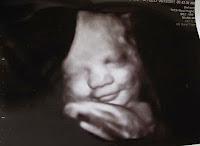

Ecografía de bebé sonriendo

Así, el antropólogo norteamericano Ray Birdwhistell, uno de los primeros especialistas en cinesis (ciencia que estudia el significado de los gestos), aseguraba: “No hay gestos universales. Que sepamos, no existe una expresión facial, una actitud o una postura corporal que transmita el mismo significado en todas las sociedades”. Pero en 2003, una investigación del obstetra estadounidense Stuart Campbell, pareció desmentir esta hipótesis.